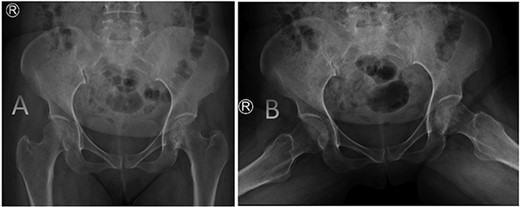

A medically free 42-year female presented to our institute as a life-saving case from a different hospital as she was a victim of unrestrained road traffic accident 2 days prior to presentation. Upon assessment in the emergency department (ER), she was conscious and oriented, and was found to have bilateral lung contusion, and multiple fractures of ribs. She also had a left sided vertical femoral head fracture dislocation comprising around 40% of the femoral head (Fig. 1). Closed reduction under conscious sedation was done in the ER, which was successful based on post-reduction imaging studies (Fig. 2). Her chest injuries were treated with chest tube and observation for 10 days. During that time, discussion was made with the patient regarding her situation and conservative management was chosen by way of bed rest and continuation of skeletal traction for 4 weeks with serial radiographs in the hospital on a weekly basis after clearance of her chest injuries. Skeletal traction was discontinued and she was advised to continue bed to wheelchair mobilization for an additional 2 weeks. After 6-weeks from the injury, a Computed Tomography (CT) was done to the patient and revealed signs of fracture healing (Fig. 3). At 3-years after the injury, she was found to have full painless range of motion of the affected hip and has resumed her activity of daily living without any complaints and the images showed a symmetrical joint space of the hips (Fig. 4).

Prereduction anteroposterior (AP) radiographs of the pelvis showing a left side fracture dislocation of the left proximal femur (A) and postreduction radiographs of the left hip (B) showing a concentric hip joint.